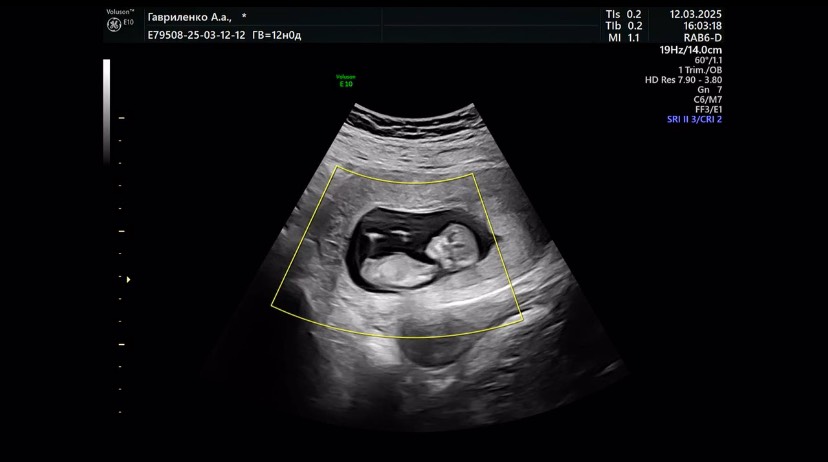

Первый скрининг пройден давно - 12 марта, все показатели в порядке. Есть периодическая тревожность в ожидании второго скрининга, потому что он только 7 мая. А в первом триместре были УЗИ на УЗИ.